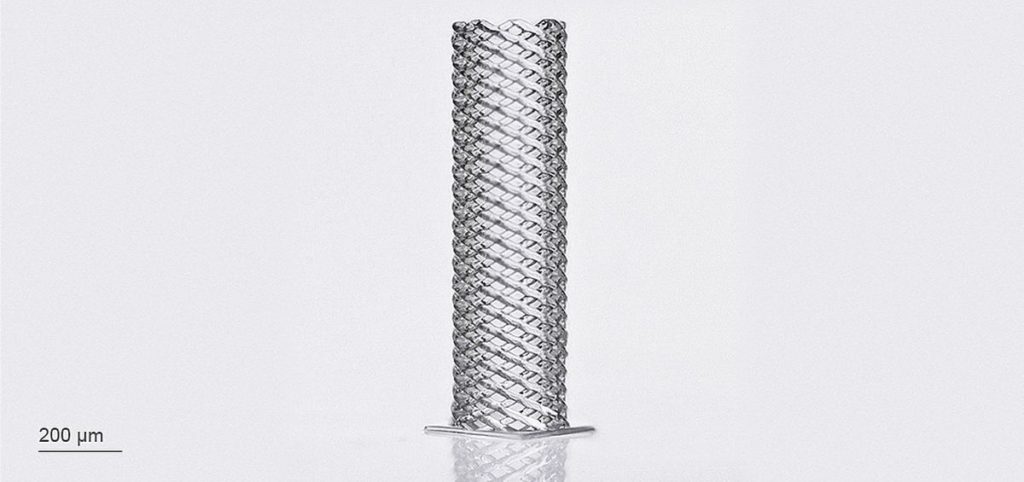

New 3D Printed Blood Vessels Could Transform Heart Bypass Operations

Researchers at the University of Edinburgh have developed a method of 3D printing blood vessels.